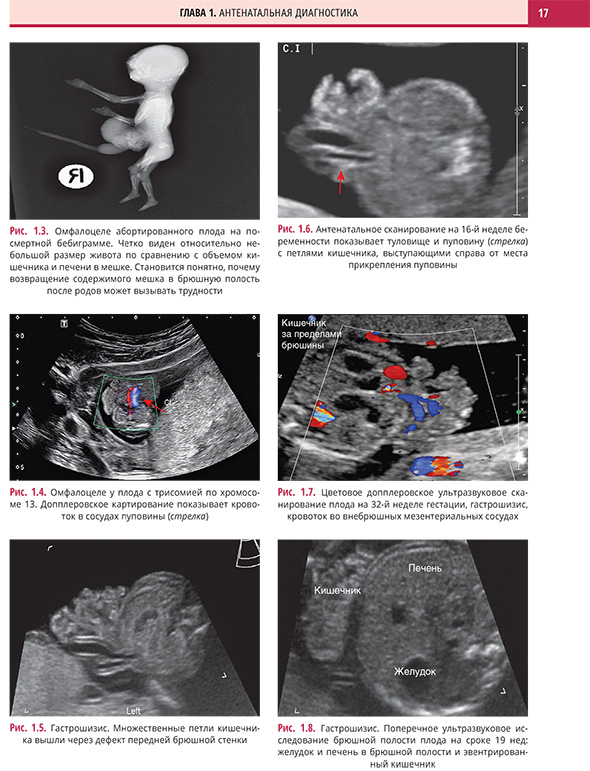

Глава 1. Антенатальная диагностика

Дефекты передней брюшной стенки